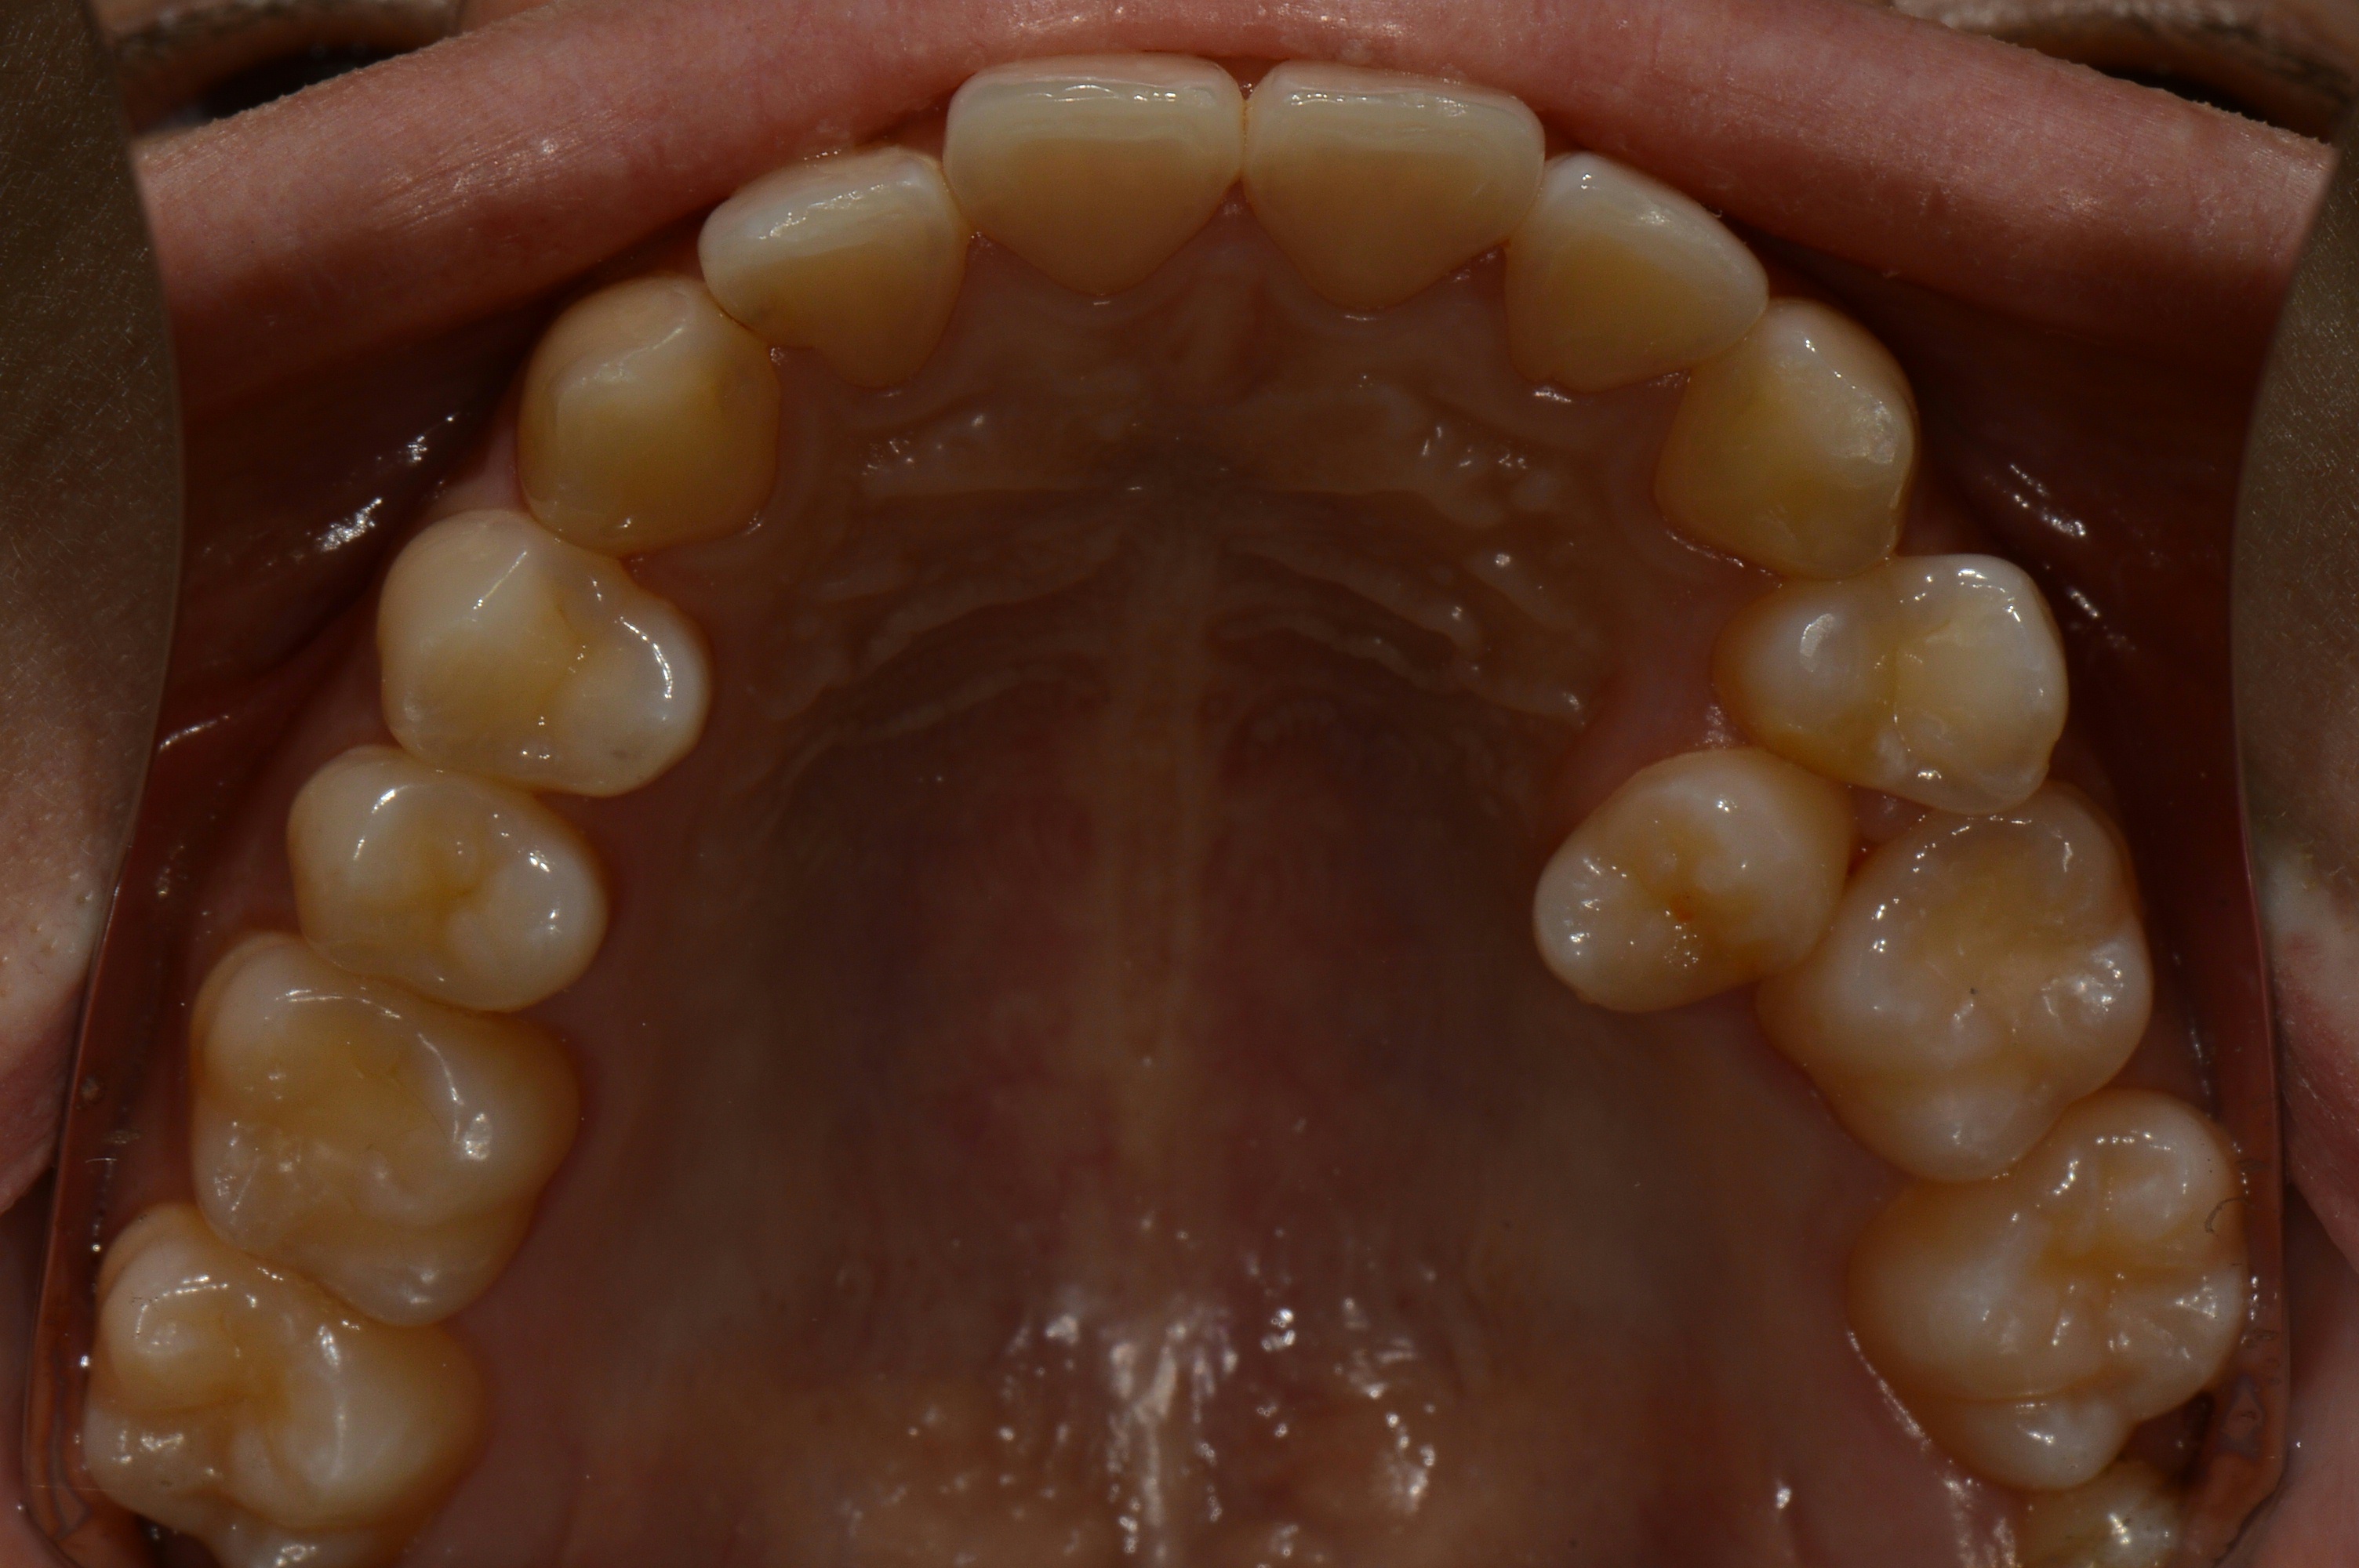

치료 후 사진입니다.